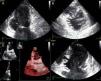

A doente foi submetida a cateterismo cardíaco, a fim de excluir doença coronária. A coronariografia revelou a presença de bridging em várias localizações da artéria coronária esquerda (descendente anterior média, ramos septais e ramos distais da primeira diagonal), também se identificando várias fístulas das coronárias esquerda e direita para o ventrículo esquerdo. Visualizava-se um trombo recanalizado no ramo póstero-lateral (fig. 1). O ecocardiograma bidimensional transtorácico mostrou hipertrofia ventricular esquerda assimétrica envolvendo principalmente o septo interventricular (22mm) e a parede lateral. Observava-se um aneurisma basal póstero-inferior. A função sistólica global encontrava-se preservada (∼55% por Simpson biplano). Na porção basal da parede septal inferior eram visíveis dois recessos intramiocárdicos em comunicação com a cavidade do VE, com cerca de 4mm de diâmetro, o maior dos quais atravessando quase toda a espessura da parede, na ausência de comunicação interventricular (fig. 2). A aurícula esquerda encontrava-se severamente dilatada, com contraste espontâneo nas cavidades esquerdas (fig. 3).

ETT (A): observa-se um aneurisma basal póstero-inferior (2D, plano apical duas câmaras). (B): são visíveis trabeculações e recessos endomiocárdicos em comunicação com a cavidade ventricular (2D, plano paraesternal, curto eixo). (C e D): na porção basal da parede septal inferior eram visíveis dois recessos intramiocárdicos em comunicação com a cavidade do VE, com cerca de 4mm de diâmetro, o maior dos quais atravessando quase toda a espessura da parede, na ausência de comunicação interventricular (imagem 2D e 3D, respetivamente, plano apical quatro câmaras).